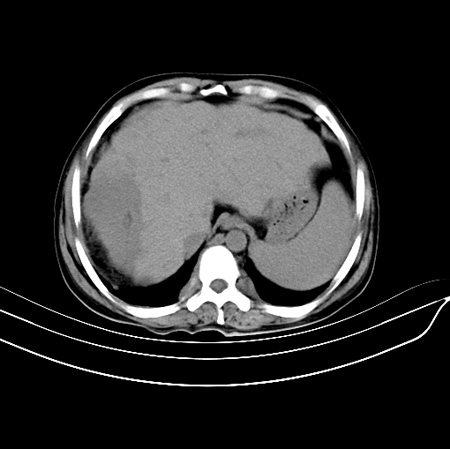

以下是引用江尾海头在2007-9-7 19:01:00的发言:[br]肝叶比例失调,肝边缘高低不平,尾状叶增大,肝裂增宽。肝右叶见较大密度减低影,边缘欠清。脾脏明显增大,胃底及奇静脉半奇静脉曲张。胆囊未见明显显示。 考虑:1、肝癌。2、肝硬化伴脾大静脉曲张。

以下是引用zhangxu5888在2007-9-7 22:31:00的发言:[br]1、肝硬化,食管 胃底及奇静脉半奇静脉曲张;2、脾脏肿大; 3、肝右叶的病灶呈锲性改变,内可见条片状钙化,边界清晰,密度明显低于周围正常肝组织,我觉得肝癌可能性不是很大, 同意楼上观点,有可能是栓塞,建议增强.